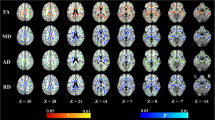

In patients with vascular MCI and SVD, MoCA score was correlated significantly with FA (positive correlation) as well as MD, AD and RD (negative correlation) in the WM tracts of almost the entire cerebral hemispheres, in an almost symmetrical fashion (Fig. 1 and Supplementary Figs. 5-7). WM tracts involved included superior and inferior longitudinal fasciculus, inferior frontal-occipital fasciculus, uncinate fasciculus, cingulum, internal capsule, forceps major and minor, corticospinal tracts and optic and thalamic radiations. MoCA score was significantly correlated with FA (positive correlation), MD and RD (negative correlation) in the WM fibers of the rostrum, body and splenium of the corpus callosum (Fig. 2).

MoCA score was also significantly correlated with FA (positive correlation) as well as MD, AD and RD (negative correlation) in the intra-thalamic WM tracts (Fig. 1 and Supplementary Figs. 5-7).

Within-group regression TBSS analysis at different anatomic levels (z coordinates in Montreal Neurological Institute standard space) in patients with vascular MCI and SVD. Yellow identifies the WM tracts showing a significant (p value <0.05 corrected, threshold-free cluster enhancement) negative correlation of MD with MoCA scores. They include WM tracts in the cerebral hemispheres, corpus callosum, thalami and decussation of superior cerebellar peduncles in the midbrain. The spatial distribution of these WM tracts is almost symmetrical. The red-yellow overlay shows the group FLAIR-lesion map. See text for abbreviations

Finally, MoCA score was significantly correlated with FA (positive correlation) as well as MD and RD (negative correlation) in the decussation of the superior cerebellar peduncles in the midbrain corresponding to the dentate-rubro-thalamic or dentate-thalamic tracts (Figs. 1 and 2 and Supplementary Figs. 5-7).

The significance maps of all DTI-derived indexes showed an intermediate degree of overlay with the group FLAIR-lesion map (Fig. 1 and Supplementary Figs. 1-7).